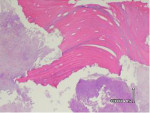

On microscopic examination, specimens typically show areas of partially or completely necrotic bone with debris and fibrinous exudates accompanied by an inflammatory infiltrate formed by neutrophils, histiocytes, eosinophils, and plasma cells. The non-vital bone exhibits loss of osteocytes from the lacunae, peripheral resorption, and bacterial colonization. Scattered sequestra and pockets of abscess formation are also commonly seen. Superficial sequestrum almost always shows necrotic bone surrounded by many bacterial colonies; utilizing special stains such as Periodic Acid-Schiff (PAS) and gram-staining can be useful to further confirm Actinomyces colonies. Studies have shown a strikingly high presence of Actinomyces in necrotic bone areas and considered these pathogens to be involved in the chronic, non-healing process of BRONJ.4 Actinomyces are commonly present as commensals in the oral cavity; thus their presence within the necrotic lesions is likely not an etiological factor in the pathogenesis of BRONJ, but rather a secondary infection of the necrotic tissues.

The patient described was classified to be in Stage III (exposed/necrotic bone, pain/infection, pathologic fracture, extraoral fistula, osteolysis to inferior border) of BRONJ. Histology revealed acute osteomyelitis showing necrotic bone and acute inflammatory infiltrate and acute and chronic inflammation of the soft tissue (Figure 15 and Figure 16). Therefore, the plan was to do a surgical resection of the diseased bone with immediate reconstruction with a bone plate.